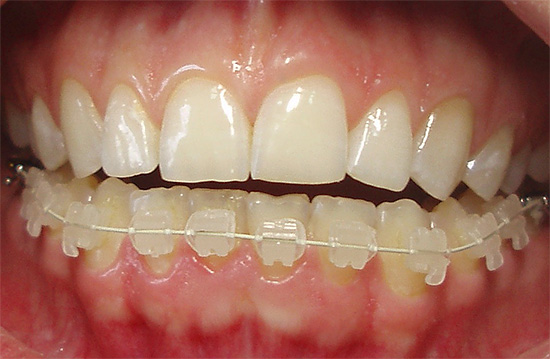

- I sistemi di staffe auto-leganti differiscono dai precedenti in quanto il design della staffa ha un coperchio che trattiene l'arco all'interno della serratura. Ciò fornisce uno scorrimento più libero dell'arco metallico lungo la dentatura, che è più comodo per il paziente, riduce il numero di visite dal medico e il tempo di trattamento. Ma tali apparecchi sono più costosi dei sistemi di legatura.

- Bretelle in ceramica - non visibili sui denti, più resistenti di quelle in plastica. Tra gli svantaggi - a causa dell'elevato grado di attrito dell'arco nel castello, il tempo di trattamento totale aumenta. Il costo di tali apparecchi è superiore a quello del metallo e della plastica.

- Bretelle in zaffiro: il più trasparente e invisibile possibile sui denti, ma molto più costoso degli analoghi.